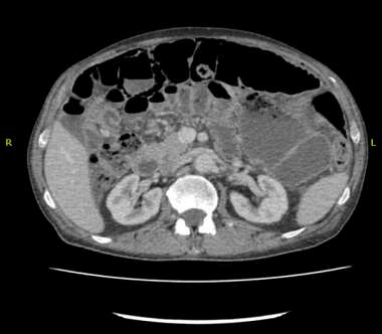

He underwent gastroscopy and colonoscopy which were normal. A CT chest, abdomen, and pelvis was then requested to exclude malignancy. However, it was reported as presence of a long segment of markedly dilated small bowel with air in the bowel wall, which appears to be the ileum. There were no peritoneal or pulmonary deposits and no definite obstructing lesion was visible. There was, however, a suspicious lesion in the ileo-cecal region. The reporting radiologist came to conclusion as distal small bowel obstruction with perforation. CXR and AXR were consistent with the findings of pneumatosis intestinalis.

Figure 2: markedly dilated small bowel with air in the bowel wall, no peritoneal disease or malignant lesions